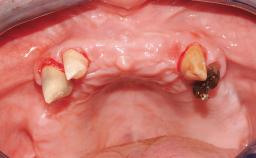

Immediate Loading of Six Implants in the Maxilla and Final Restoration with a Full-Arch CAD/CAM Zirconia FDP

A 63-year-old male patient was referred for a consultation and treatment of partial edentulism in the maxilla. The patient presented with residual anterior teeth and declined a partial removable prosthesis. He reported that the maxillary posterior teeth had been extracted due to mobility and periodontal disease two months before the consultation. The patient’s chief complaint was that his residual maxillary teeth were mobile and that he was unable to chew. The patient’s desire was a stable and comfortable fixed maxillary rehabilitation. The patient was a light smoker (fewer than 10 cigarettes/ day), and his medical history was without significant findings. He was not on any regular medication at the time of consultation. The extraoral examination revealed a normal physiognomy with a correct distribution of the facial thirds. The patient presented a low lip line, and the transition line between teeth and soft tissues was not exposed during a forced smile.

Soft Tissue Anatomy Intact Defective

Soft Tissue Contour and Volume Slightly compromised